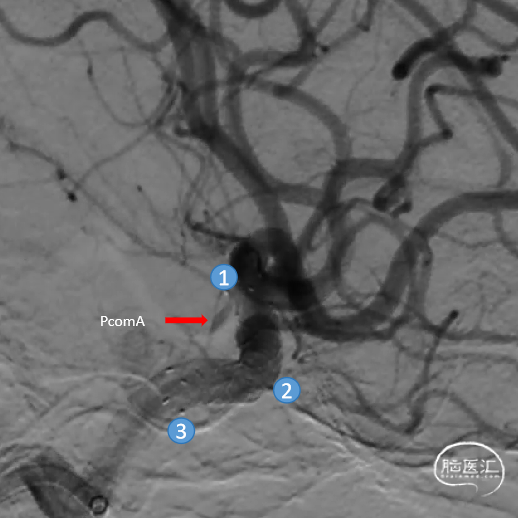

术中DSA造影:右侧颈内动脉正、侧位造影,显示右侧颈内动脉床突旁大型动脉瘤。

术中DSA造影:右侧颈内动脉3D造影提示:右侧颈内动脉床突旁大型动脉瘤,大小约为20.72×16.33mm,远端血管直径1.92mm,近端血管直径3.48mm。

①输送导丝头端

②支架远端显影点

③支架微导管头端